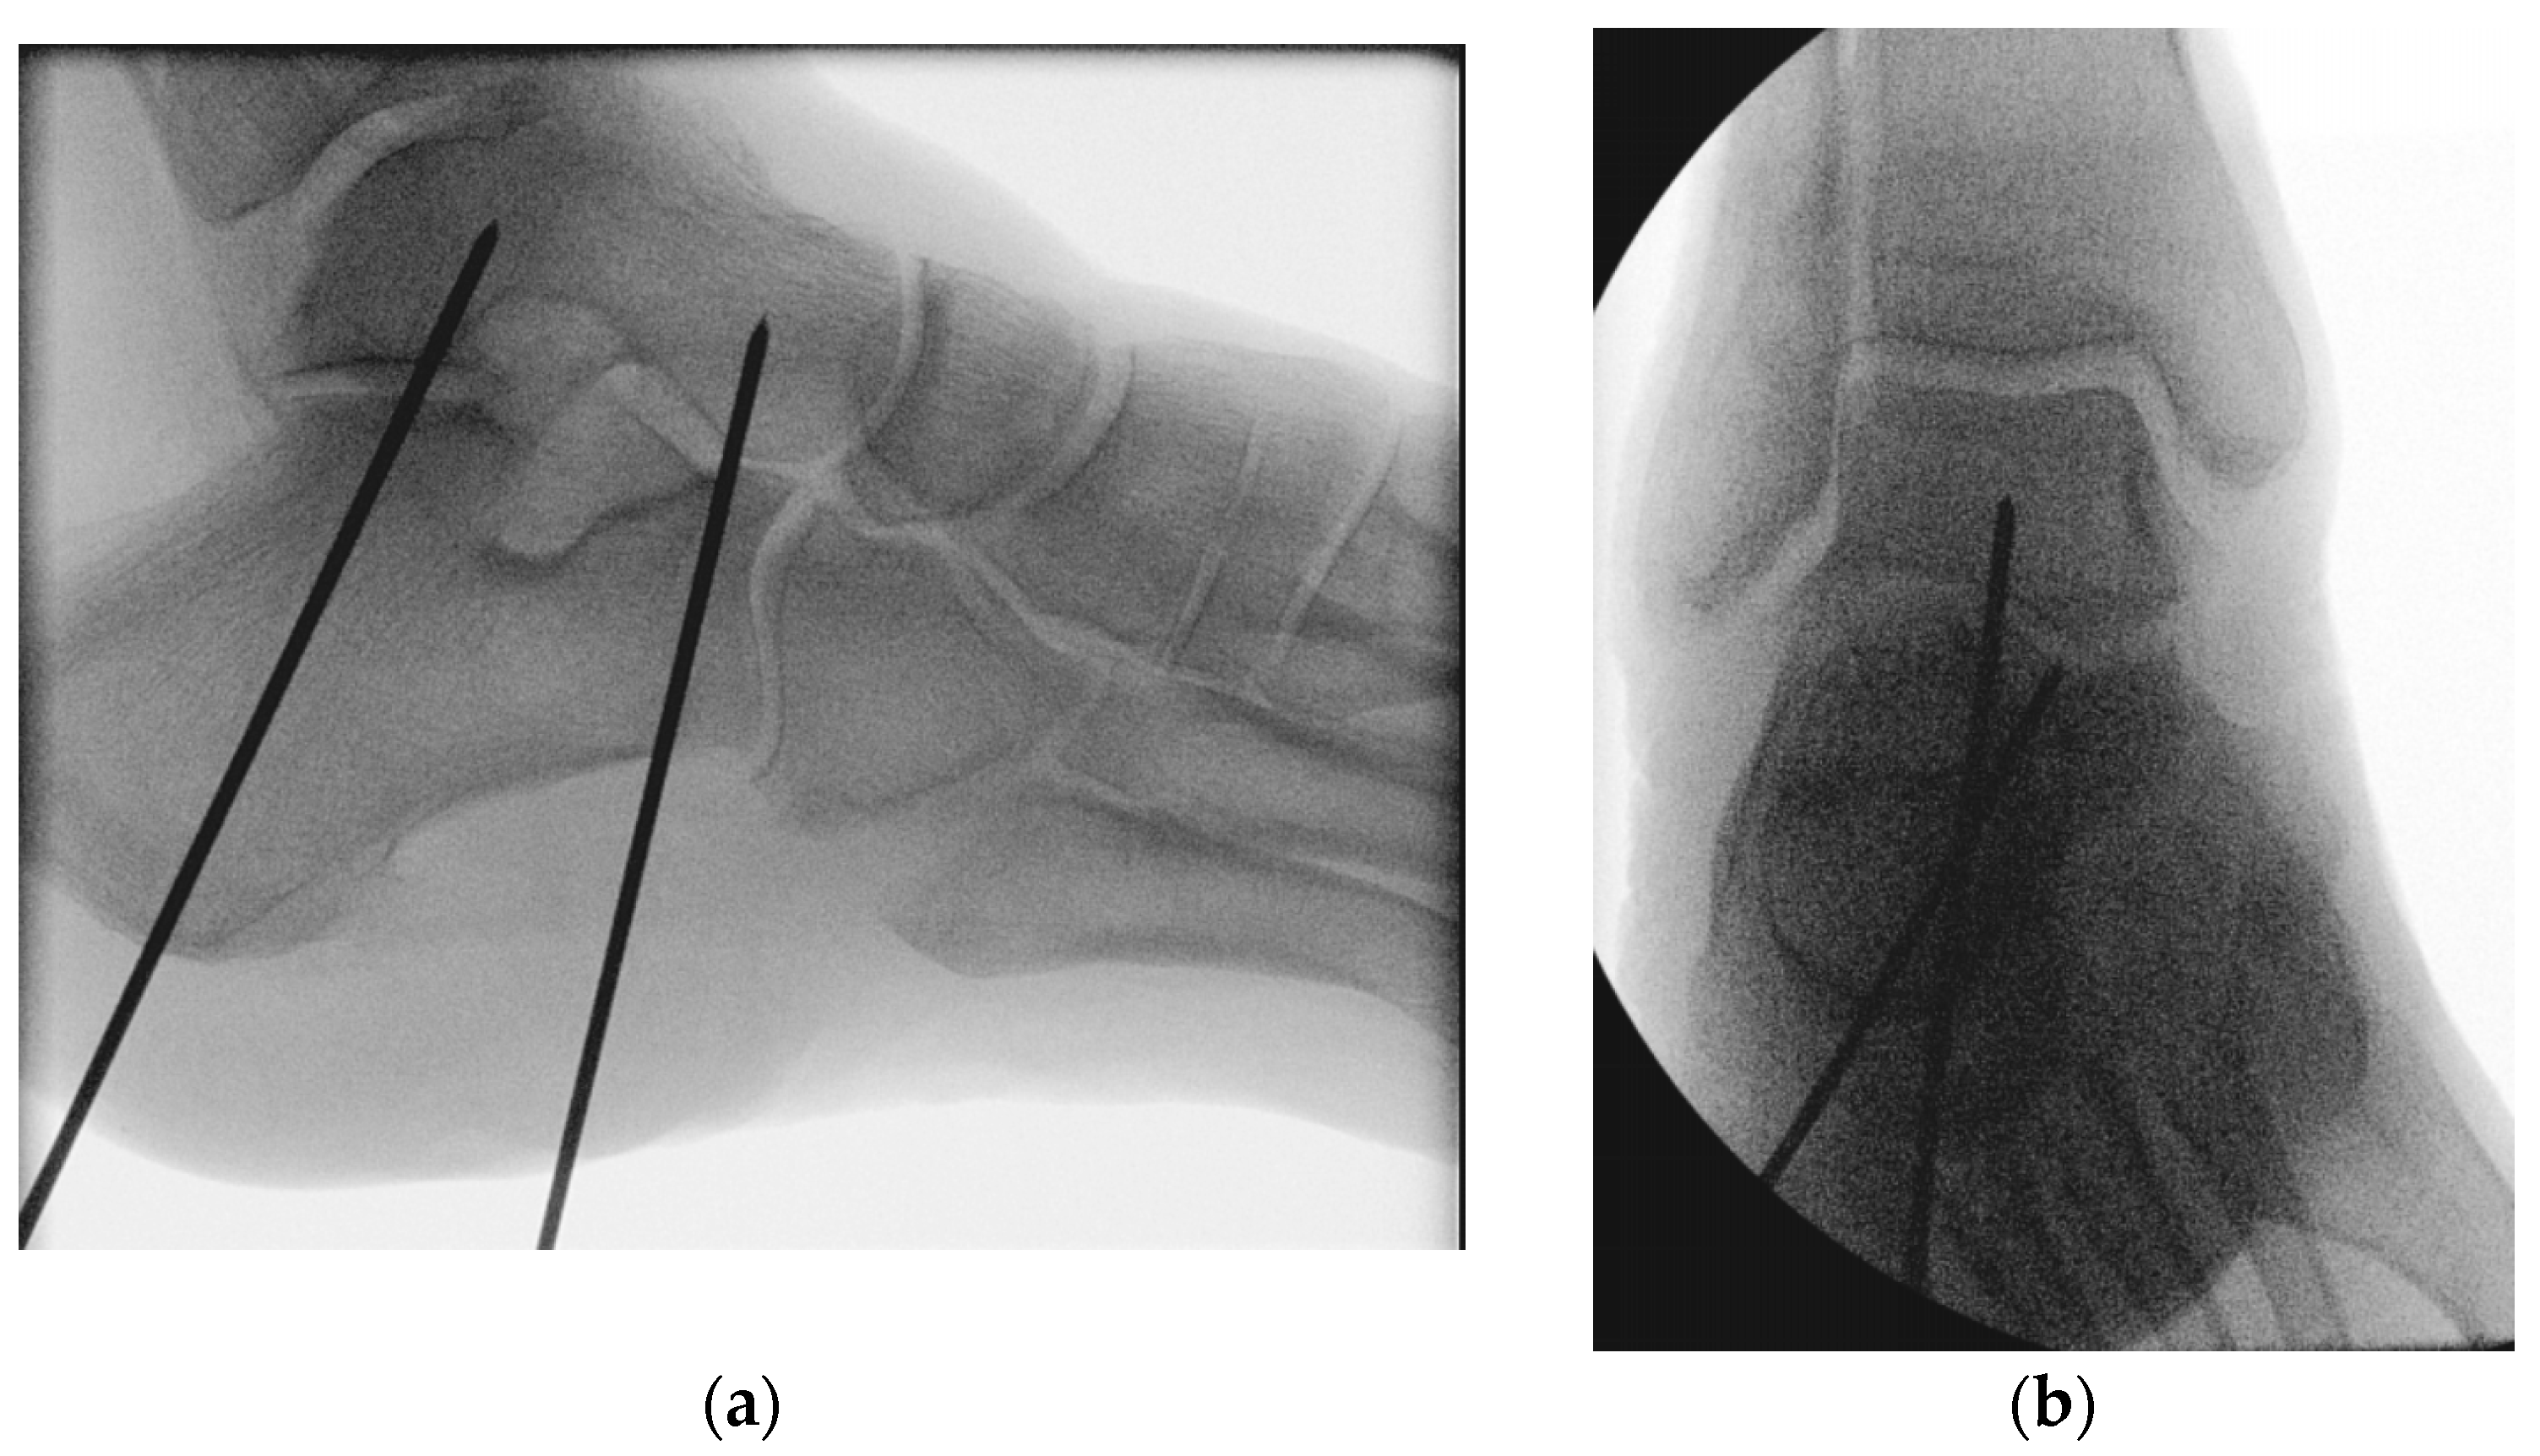

2. Materials and Methods

2.1. Specimens and Preparation

2.2. Biomechanical Testing